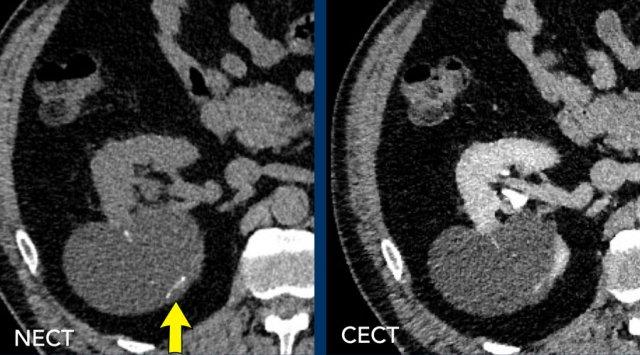

Hình ảnh

Tổn thương 1 (mũi tên vàng)

Quan sát thấy một tổn thương đồng nhất, giảm tỷ trọng ở mặt sau thận phải. Tổn thương này quá nhỏ để phân loại và được xếp vào nhóm Bosniak II.

Tổn thương 2 (mũi tên trắng)

Trên CT không tiêm thuốc cản quang (NECT), có một tổn thương tăng tỷ trọng ở thận trái với HU > 70, thông thường tương ứng với tổn thương Bosniak II (mũi tên trắng). CT có tiêm thuốc cản quang (CECT) trong pha tĩnh mạch cửa không cho thấy sự ngấm thuốc đáng kể nhưng có hình ảnh không đồng nhất.

Trường hợp này cần chụp thêm MRI để đánh giá bổ sung (xem hình ảnh tiếp theo).